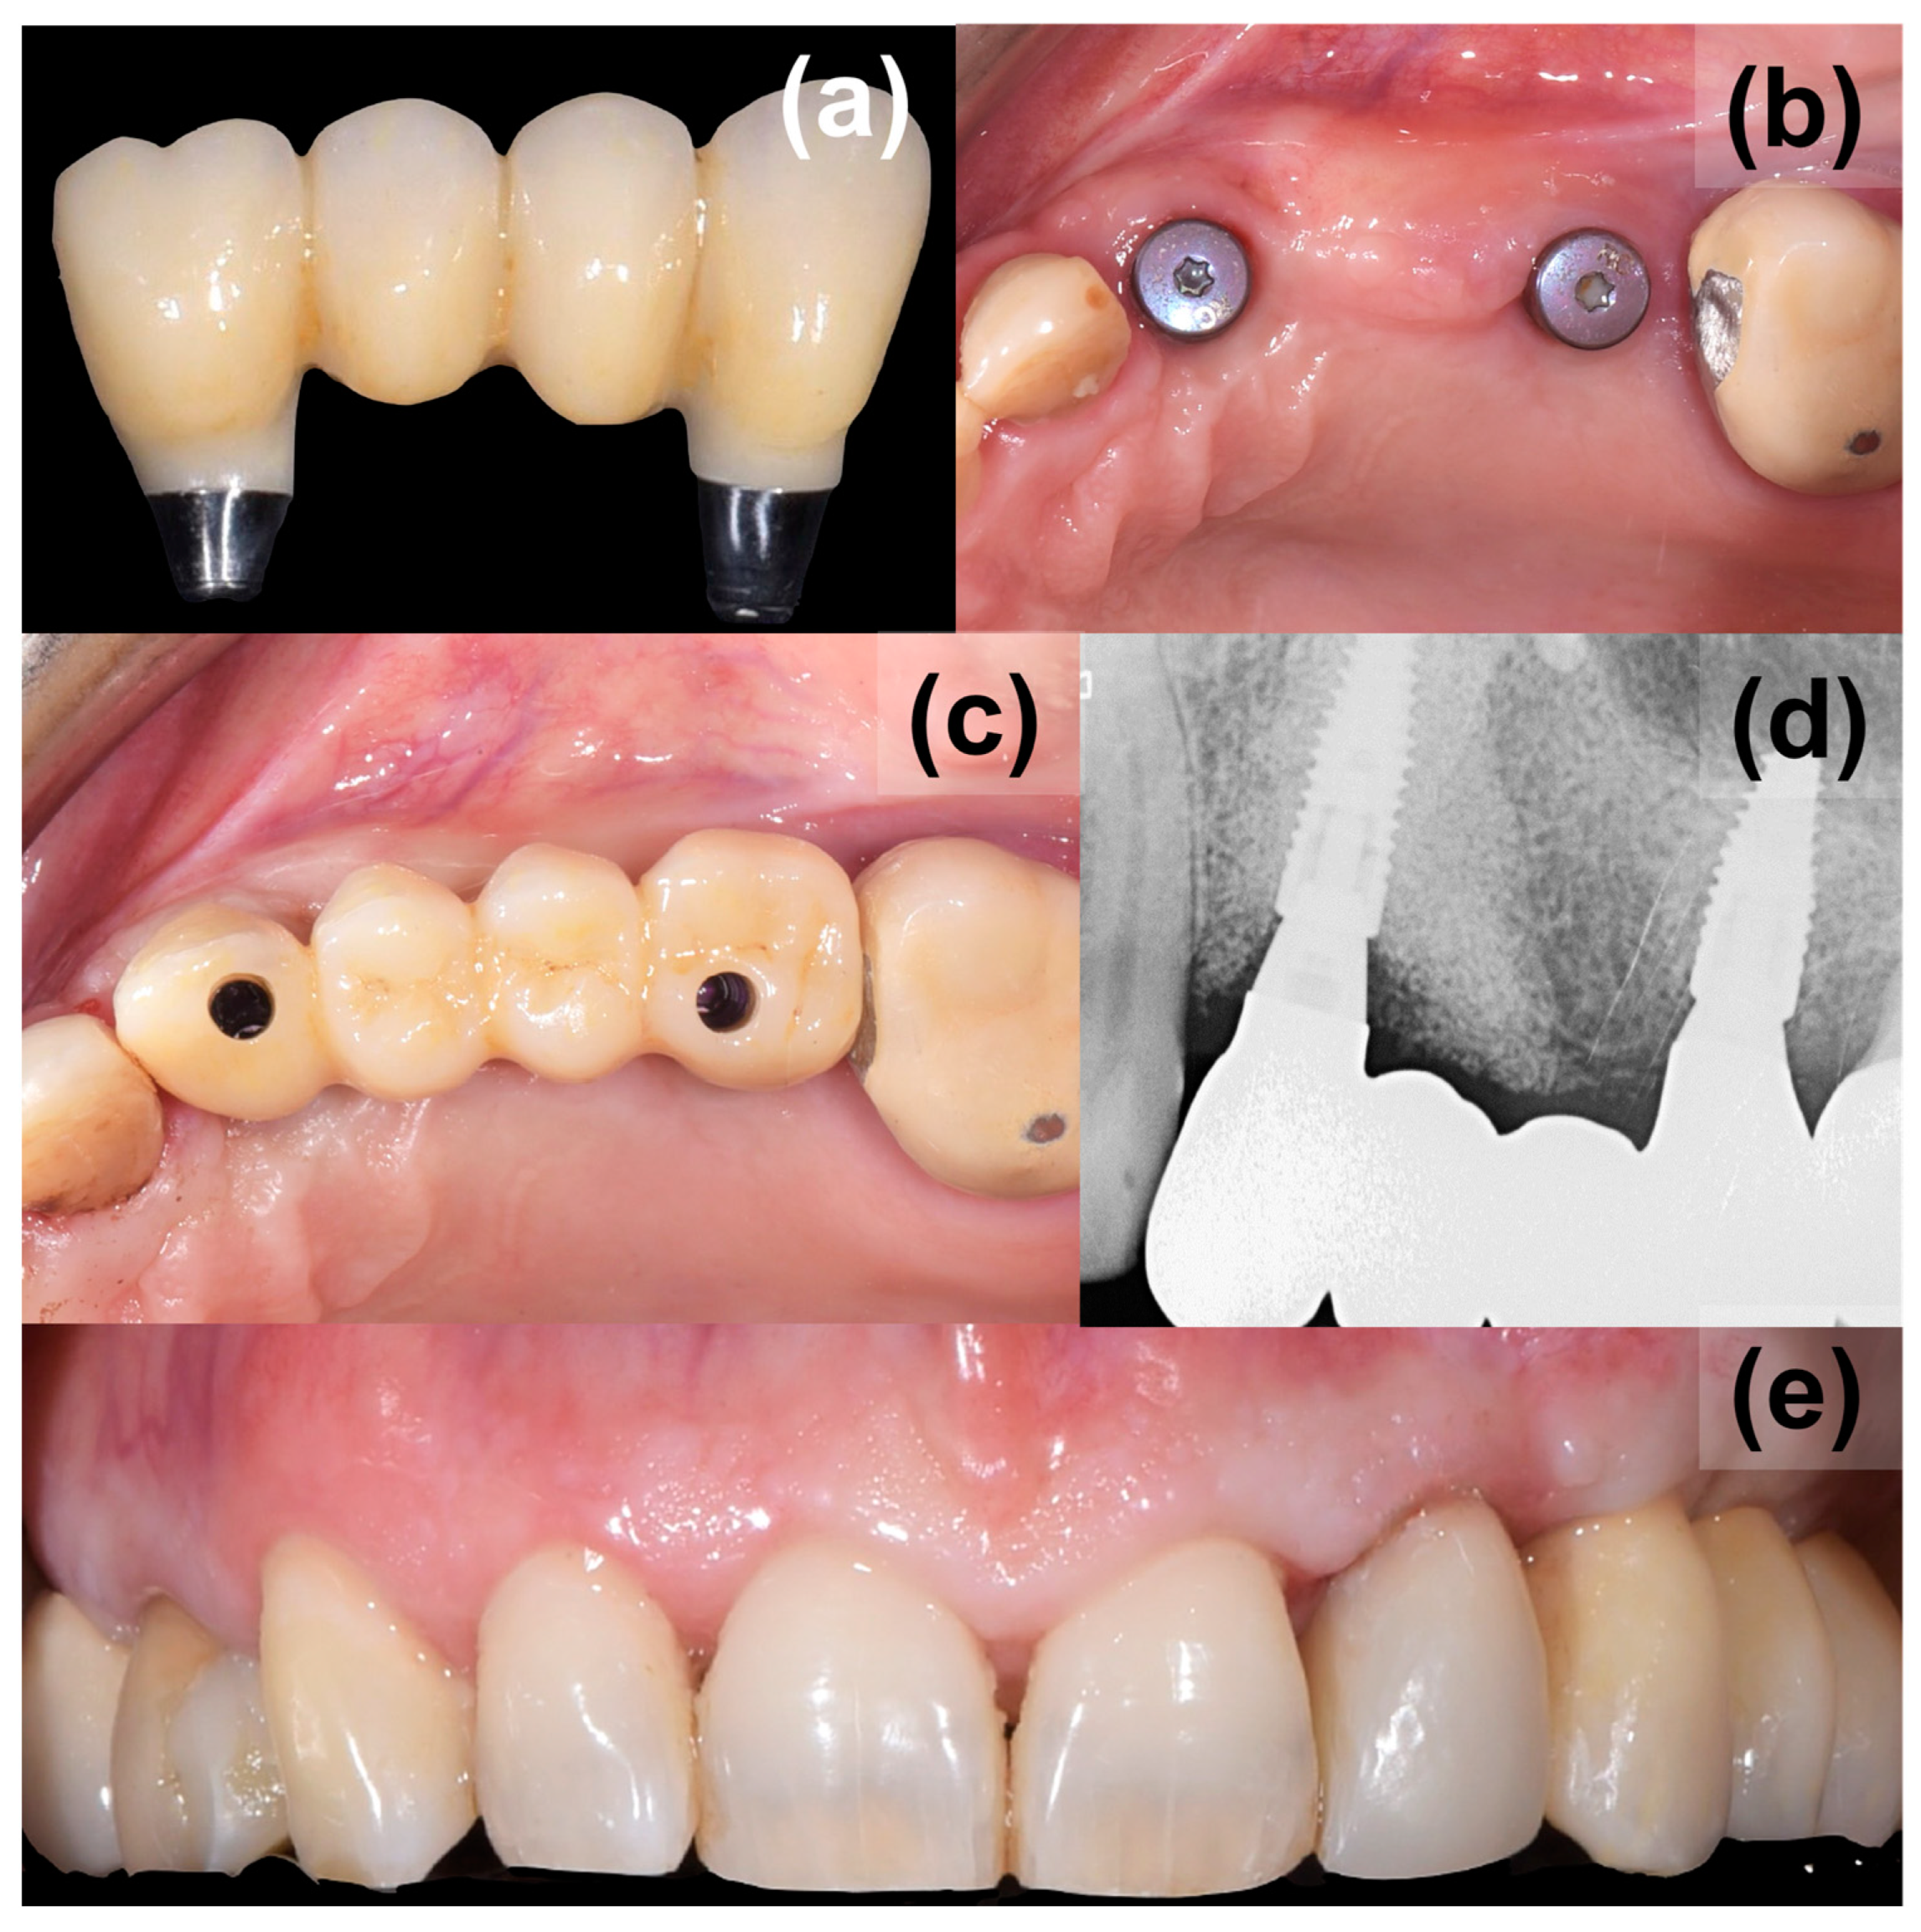

2. Case Presentation